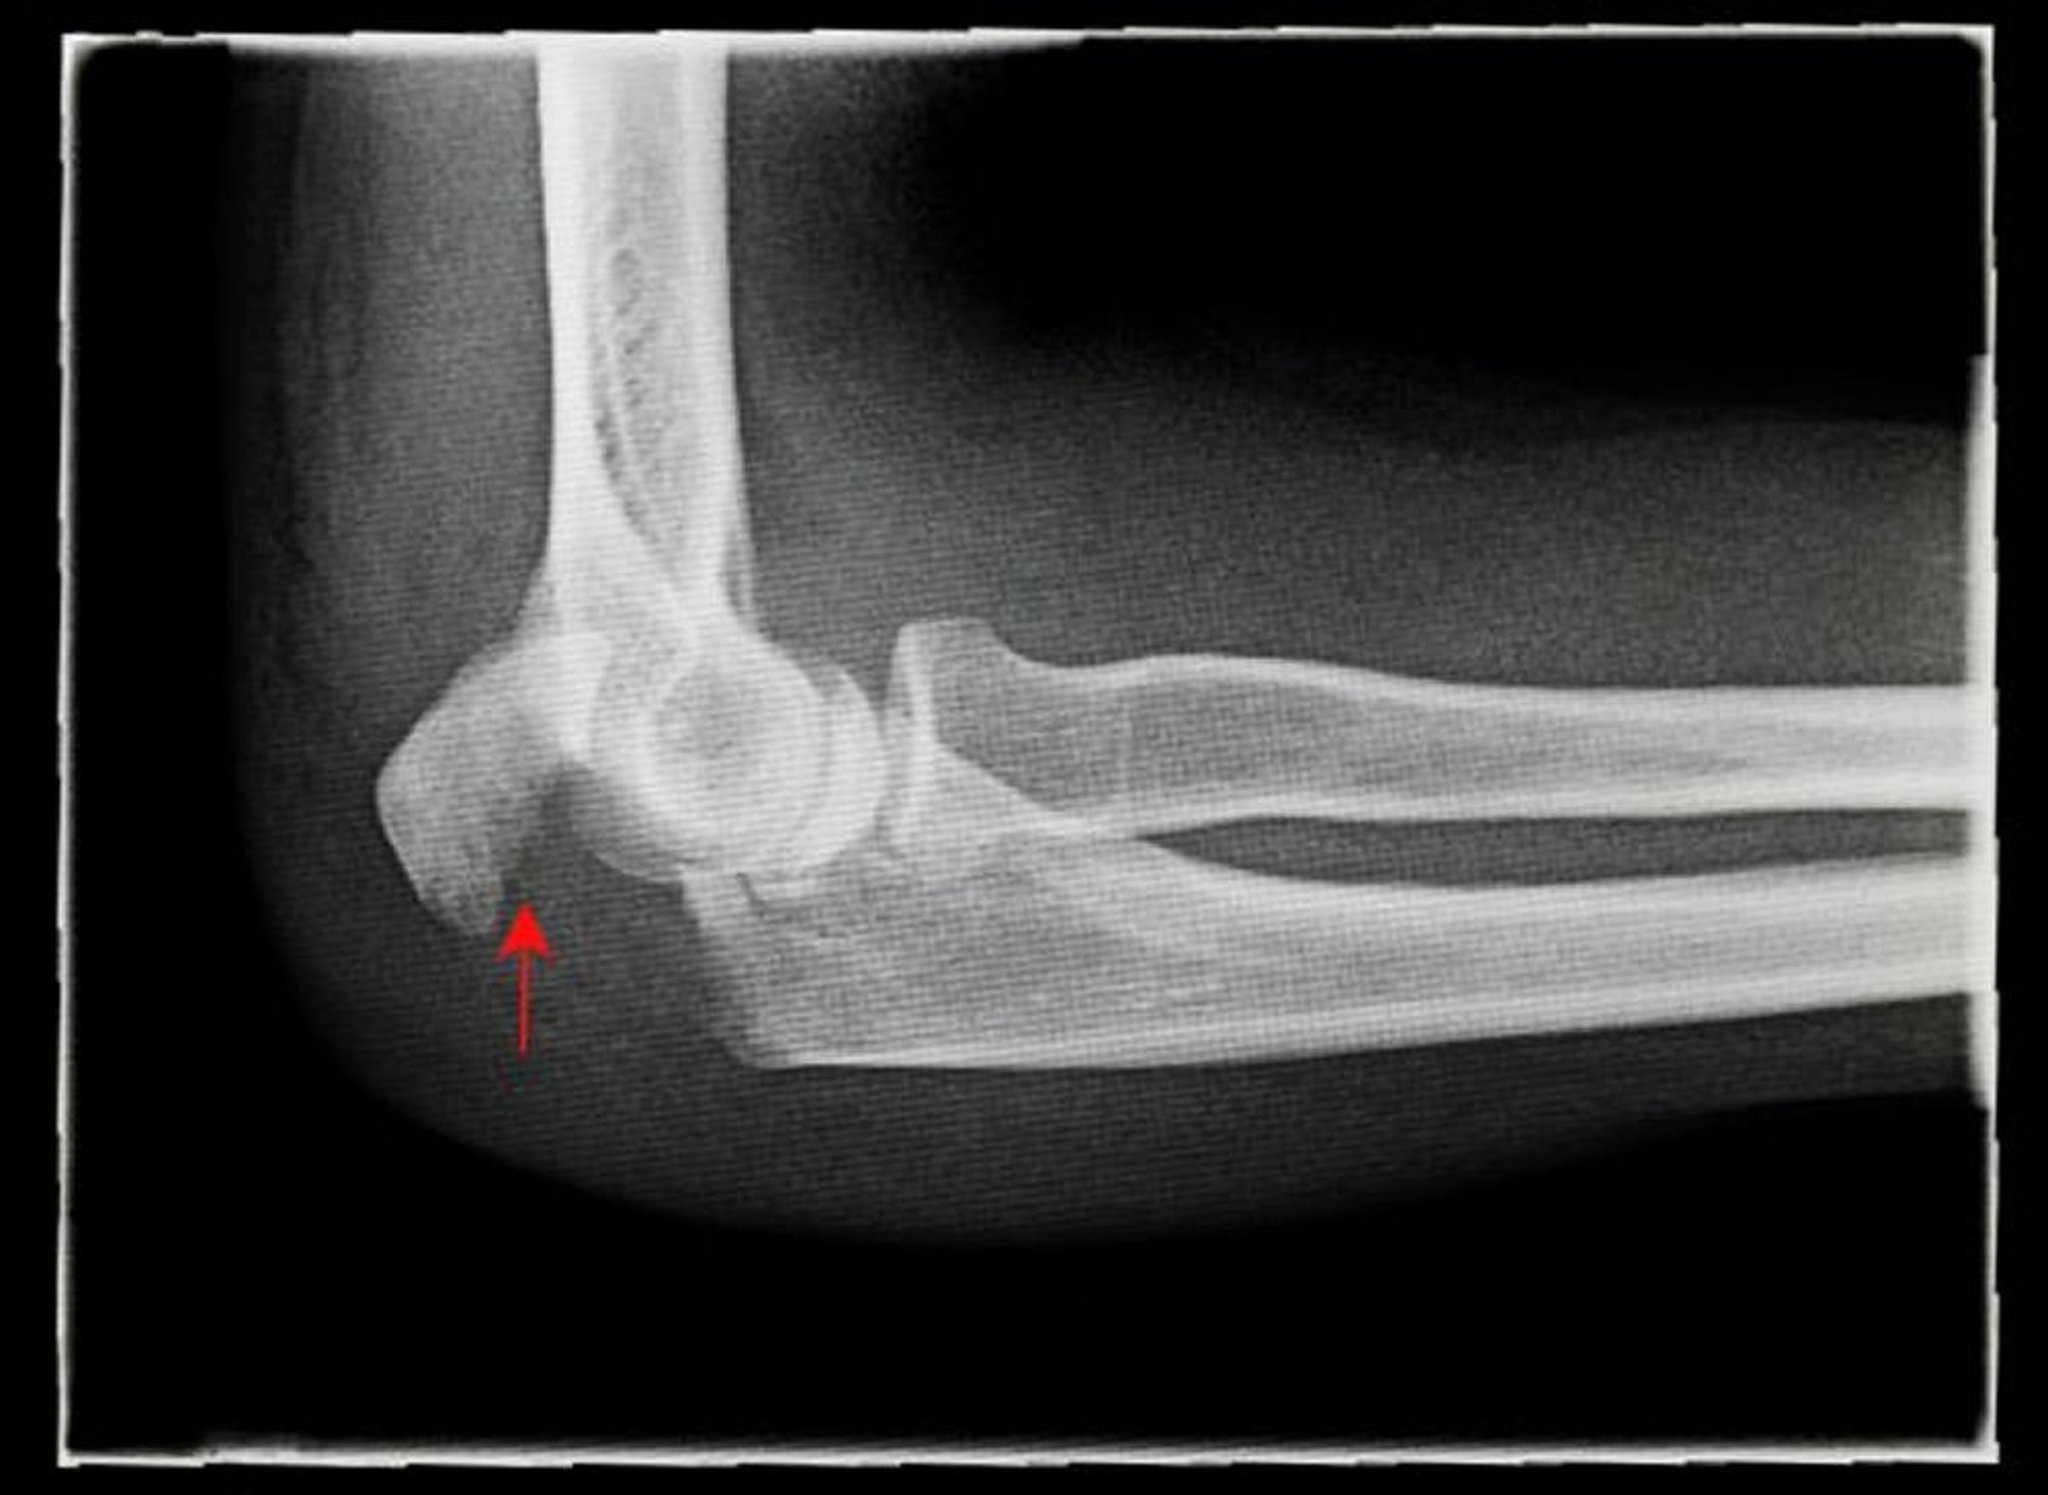

Перелом ліктьового відростка

Рентгенографія у бічній проекції демонструє перелом ліктьового відростка зі зміщенням (стрілка).

Подяка: АНТОНІЯ РІВ (ANTONIA REEVE)/НАУКОВА ФОТОБІБЛІОТЕКА